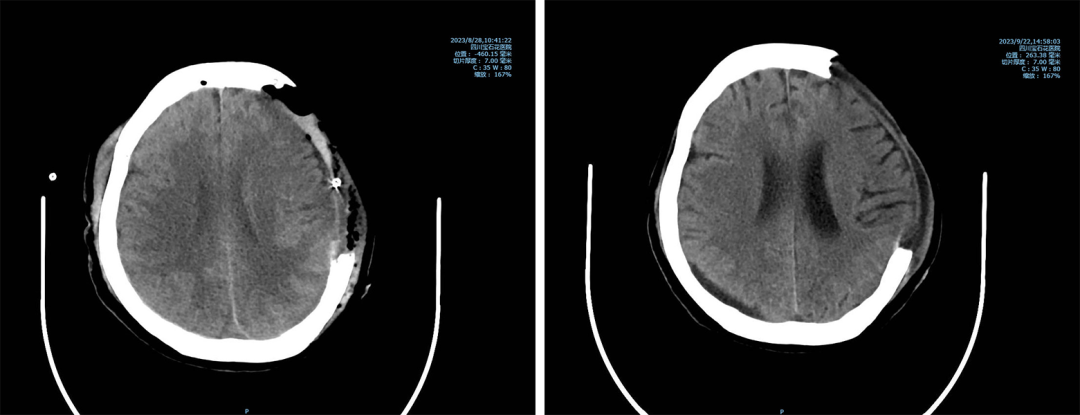

然而,老人因车祸导致全身多处内脏损伤、骨折,随后在医院多专业医护人员的齐心协力下,又相继经历了创伤后重症肺炎呼吸机救治、脓毒血症、低蛋白血症、大量胸腔积液、腹腔积液、植入物局部排异等重重难关。

可谓是关关难过,关关过。吴婆婆因病情起伏变化,总共经历了三次开颅手术,每一次手术,每一条诊疗策略都是对医生技术、体力与决策的考验,更是对医患双方信任的考验。

四川宝石花医院神经外科的医护团队始终保持着高度的责任心与使命感,夜以继日地守在吴婆婆的病床旁。他们密切关注着老人的病情变化,如细心的哨兵观察着瞳孔的细微变化,精准地测量尿量,精心护理引流管,及时调整治疗方案,力求针对老人的具体情况,每一步都走得沉稳而有效。